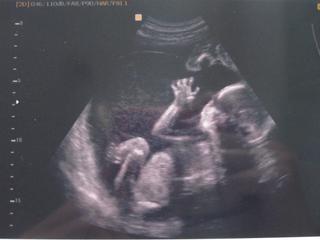

Zdá se mi, že podle některých jiných fotek, které tady vidím, jsou ty jeho už celkem ostré.. Např. chlapeček ve 20 tt:

@kanegoo To je krásná fotečka!!! A je to pěkně ostrý..

Já ani tentokrát takovýhle pěkný nemám..pořád jsem se na vyšetření bála, jestli se něco nepokazilo, tak jsem se nikdy o fotku ani nepřihlásila..mám jen fotečky bublinek na začátku a pak až pěkný fotky z 3Dutz, kde kluci vypadají jako kopie prvního synka, tak jsem zvědavá, jestli je budu mít fakt jako přes kopírák 😀